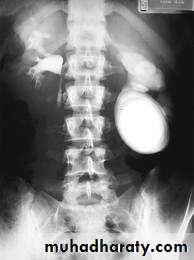

Schistosomiasis

Infestation by s.hematobium

Calcification is most important feature, mainly in bladder & lower ureters , but may involve whole ureters .

In early stage inflammation may cause cobble stone appearance.

Bladder capacity not affected.Ddgx of bladder calcification :

1. schistosomiasis .2.tumor , TB, …